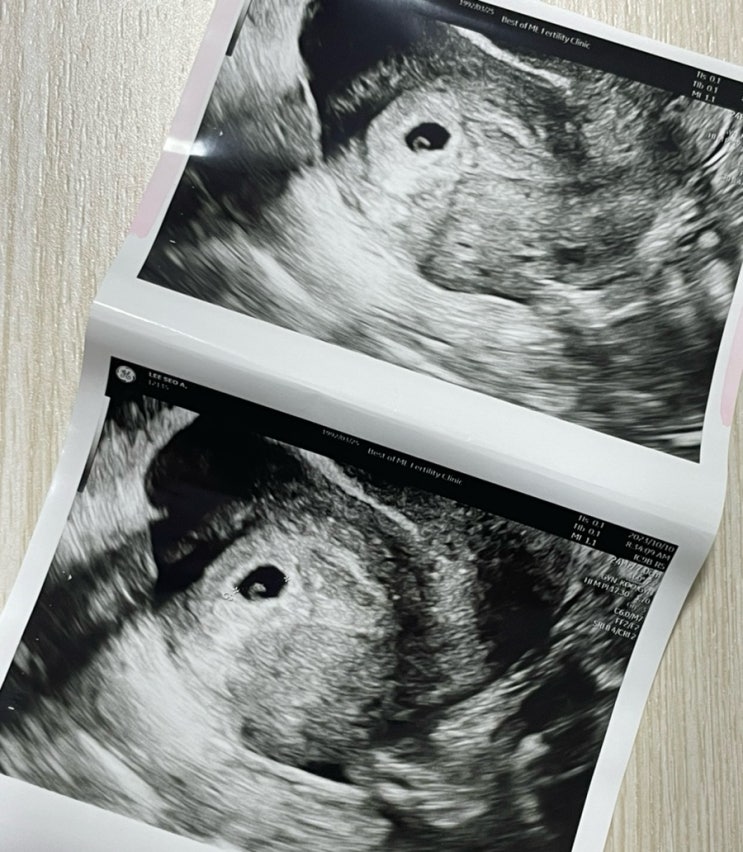

임신 8주차 이때 볼수있는 젤리곰!!! 보기위해 베스트오브미여성의원에 갔다 아직 난임병원을 다니는 중이...

난임일기/자연주기-4일배양/아기집확인,출산예정일

2차 피검까지하고 드디어 아기집 확인하러 다녀왔다 ! 얼마나 떨리던지 아기집은 잘 컸는지 난황은 생겼는...